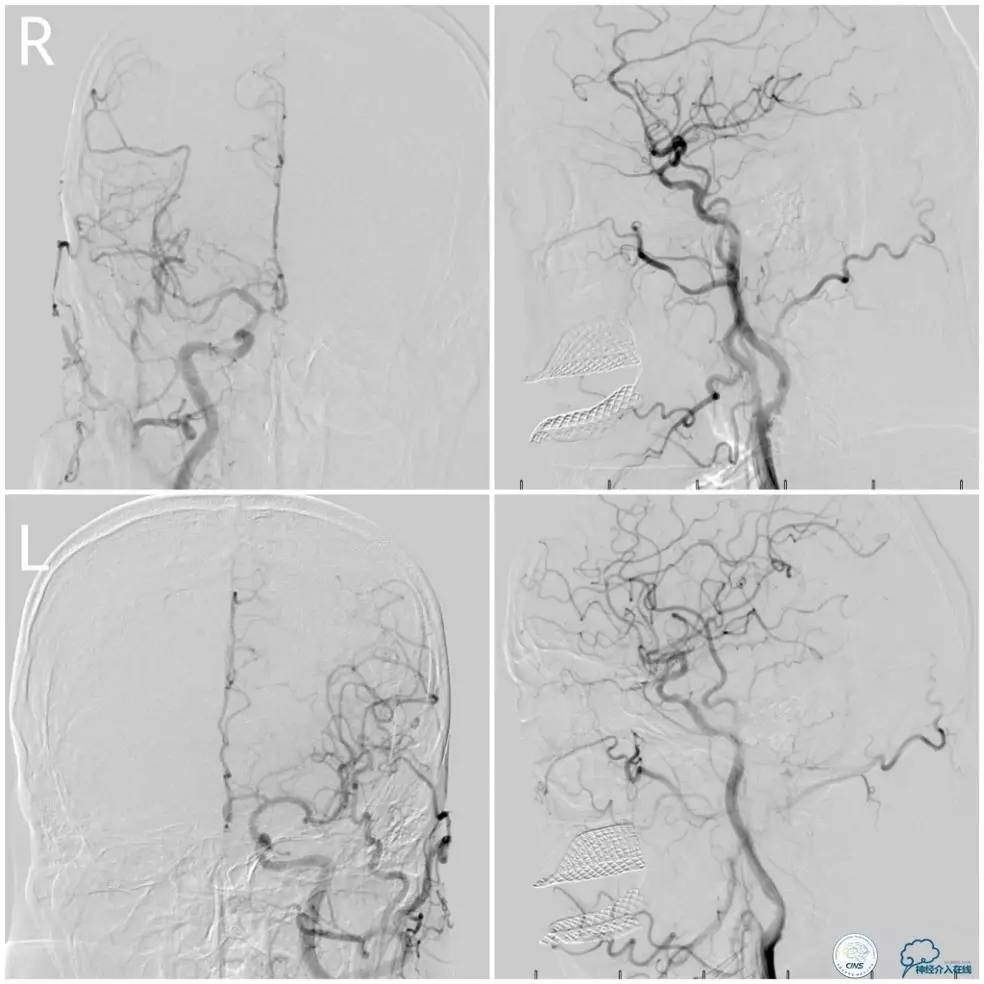

术前DSA:右椎动脉V1段长段重度狭窄,V4-基底动脉交界区显影浅淡,狭窄程度重,但具体程度显示欠佳(图7)。左椎动脉V1段闭塞,左椎动脉V2远段经侧支代偿显影,V3段以远未见显影(图8)。前循环造影未见明显前循环向后循环代偿(图9)。

图7

图8

图9

1. 患者右椎动脉优势,右椎动脉V1段长段重度狭窄、V4段-基底动脉重度狭窄(或者闭塞)。左椎动脉V1段闭塞,经侧支代偿的左椎动脉V3段以远未见显影亦考虑闭塞,拟处理右椎动脉。

2. 右椎动脉V1段狭窄程度重,病变长度长,但病变血管较为平直,估计先处理近端病变后导引导管越过支架难度不大,故决定先处理近端病变再处理远端病变。

3. 右椎动脉V4段-基底动脉长段狭窄,CT提示局部钙化明显,预计发生术中扩张困难的机率高,拟采用球囊预扩张,再放置自膨支架。